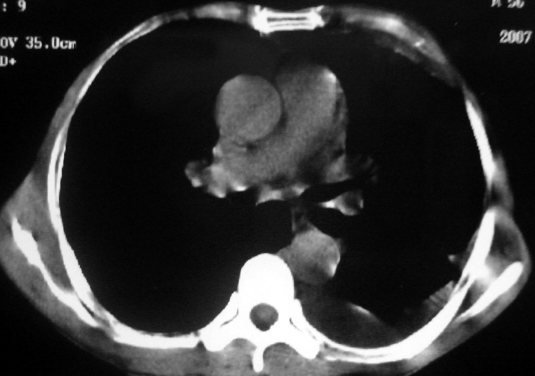

男,54岁,咳嗽,气喘半年,胸痛一月.

血性胸水

支持左肺下叶中心型肺癌(累及舌叶)伴阻塞性肺炎、膨胀不全、胸腔积液、心包少量积液。

考虑左肺下叶中央型肺癌伴阻塞性肺炎及肺不张,纵隔受累可能,胸膜转移。